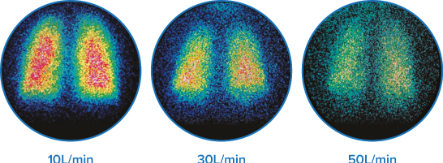

- 3.5%–17% 的药物肺内沉降率,具体取决于流速†6

健康成人中不同流速(10、30 和 50 L/分钟)下的雾化药物肺内沉降图。†6